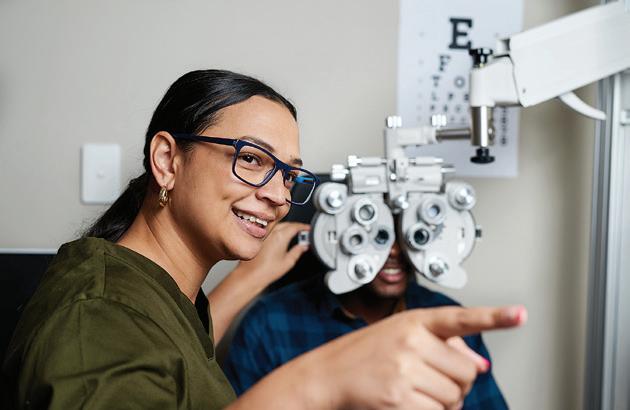

At Estes Park Health, we know you’d rather spend your time enjoying the beauty of Estes Valley — not traveling for special medical care. That’s why we bring specialty care to you. With more than 20 medical specialties available right here in your community, you get the expert diagnosis and compassionate treatment you need without leaving town.

Oncology Ophthalmology Orthopedic Surgery Pediatrics & Infusion Dermatology

Fa y g y Internal Medicine Neurology

Podiatry Pulmonology (including Asthma & CPAP fittings)

Respiratory Therapy Sleep Lab Urology

Estes Park Health also provides:

Diagnostic Imaging Rehabilitation Laboratory Services